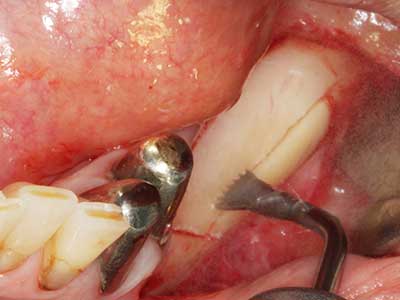

Fig. 19: Zona operada después de neurolisis y eliminación del osteomo.

Fig. 20: La tapa ósea extraída se readapta y se fija mediante un tornillo para osteosíntesis (KLS Martin, Tuttlingen).